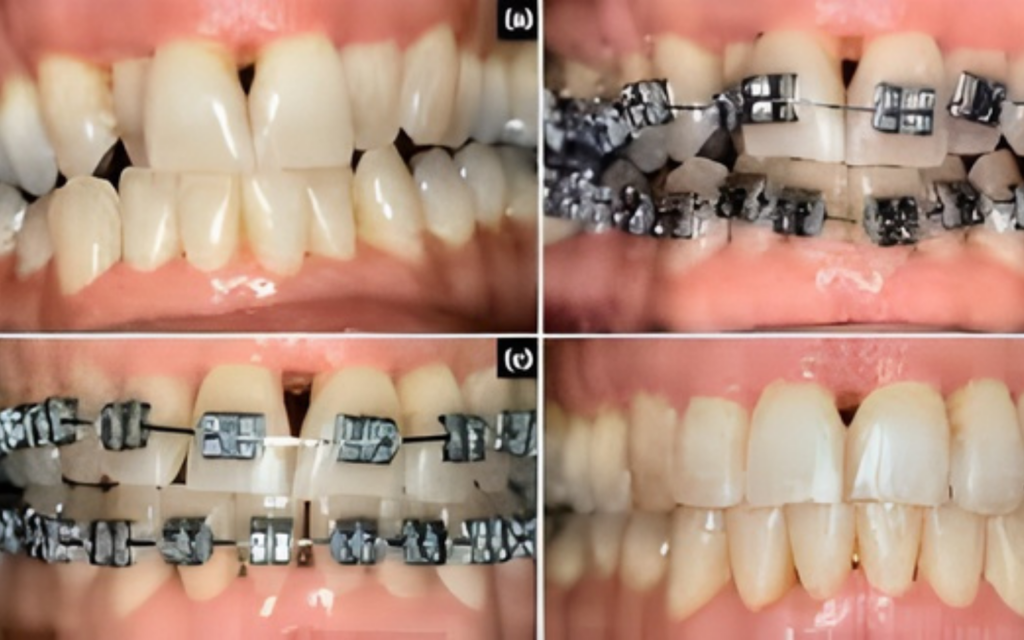

ORTHODONTIC BRACES

Orthodontic treatments move the teeth to their correct position, improve your smile and surrounding facial structures such as your jaw